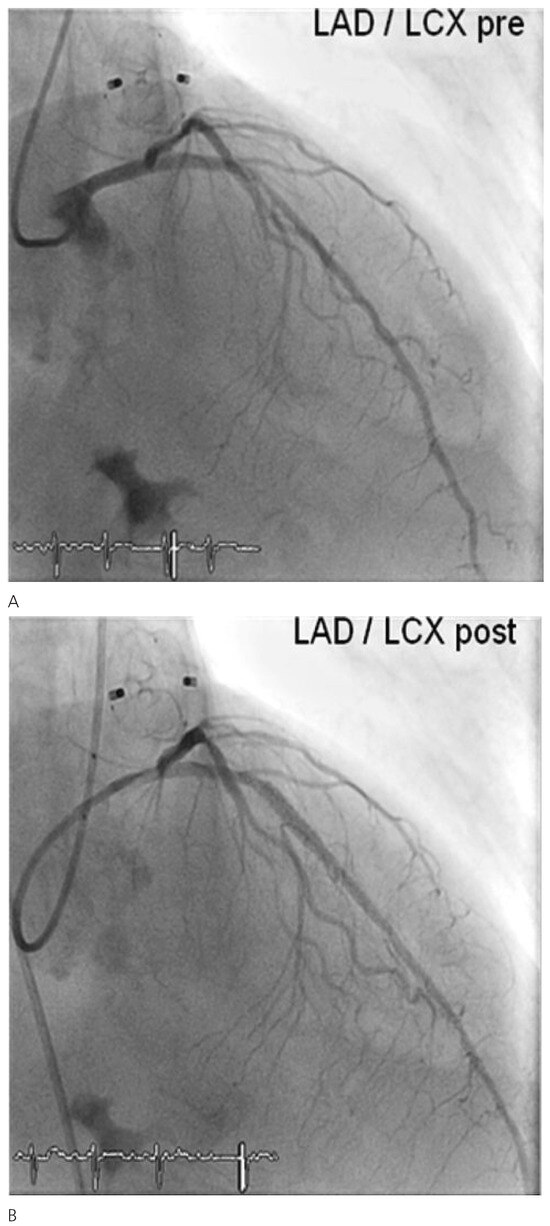

Case Report

Comprehensive “One Stop-Shop” Percutaneous Cardiac Intervention

by Thomas Pilgrim, Peter Wenaweser, Stephan Windecker and Bernhard Meier

Cardiovasc. Med. 2010, 13(5), 171; https://doi.org/10.4414/cvm.2010.01497 - 26 May 2010

A 78-year-old male retired mathematician with severe aortic stenosis, persistant atrial fibrillation, reluctance to accept oral anticoagulation, and with suspected coronary artery disease was referred for further management [...] Full article

Show Figures

Figure 1